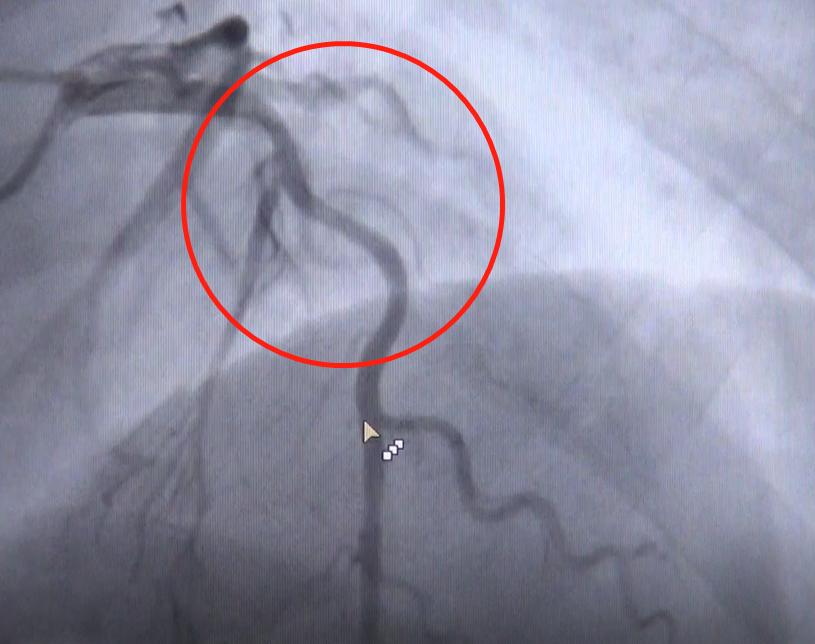

造影的结果,如同他4月份在老家医院一样:前降支的近中段位置,预估大概狭窄50~60%,确实不明显。后来医生打了硝甘,把血管尽量扩开之后,评估出最大狭窄程度,也只70%这个水平。

不过,按照生理结构特点推断,冠脉血管应该是由粗逐渐变细,越来越细的生理结构。而老宋的血管,好像上下一样粗,中间部分突然间收缩了。

医生判断,这支血管病变范围是比较广的,比较弥漫均匀,所以才会导致看着还可以的错觉。